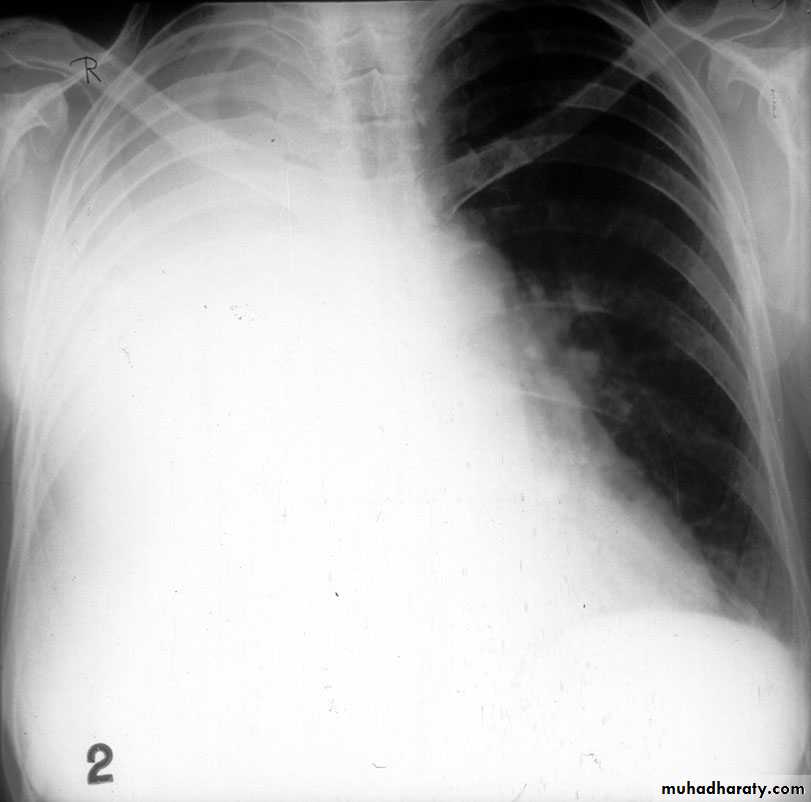

Massive pleural effusion